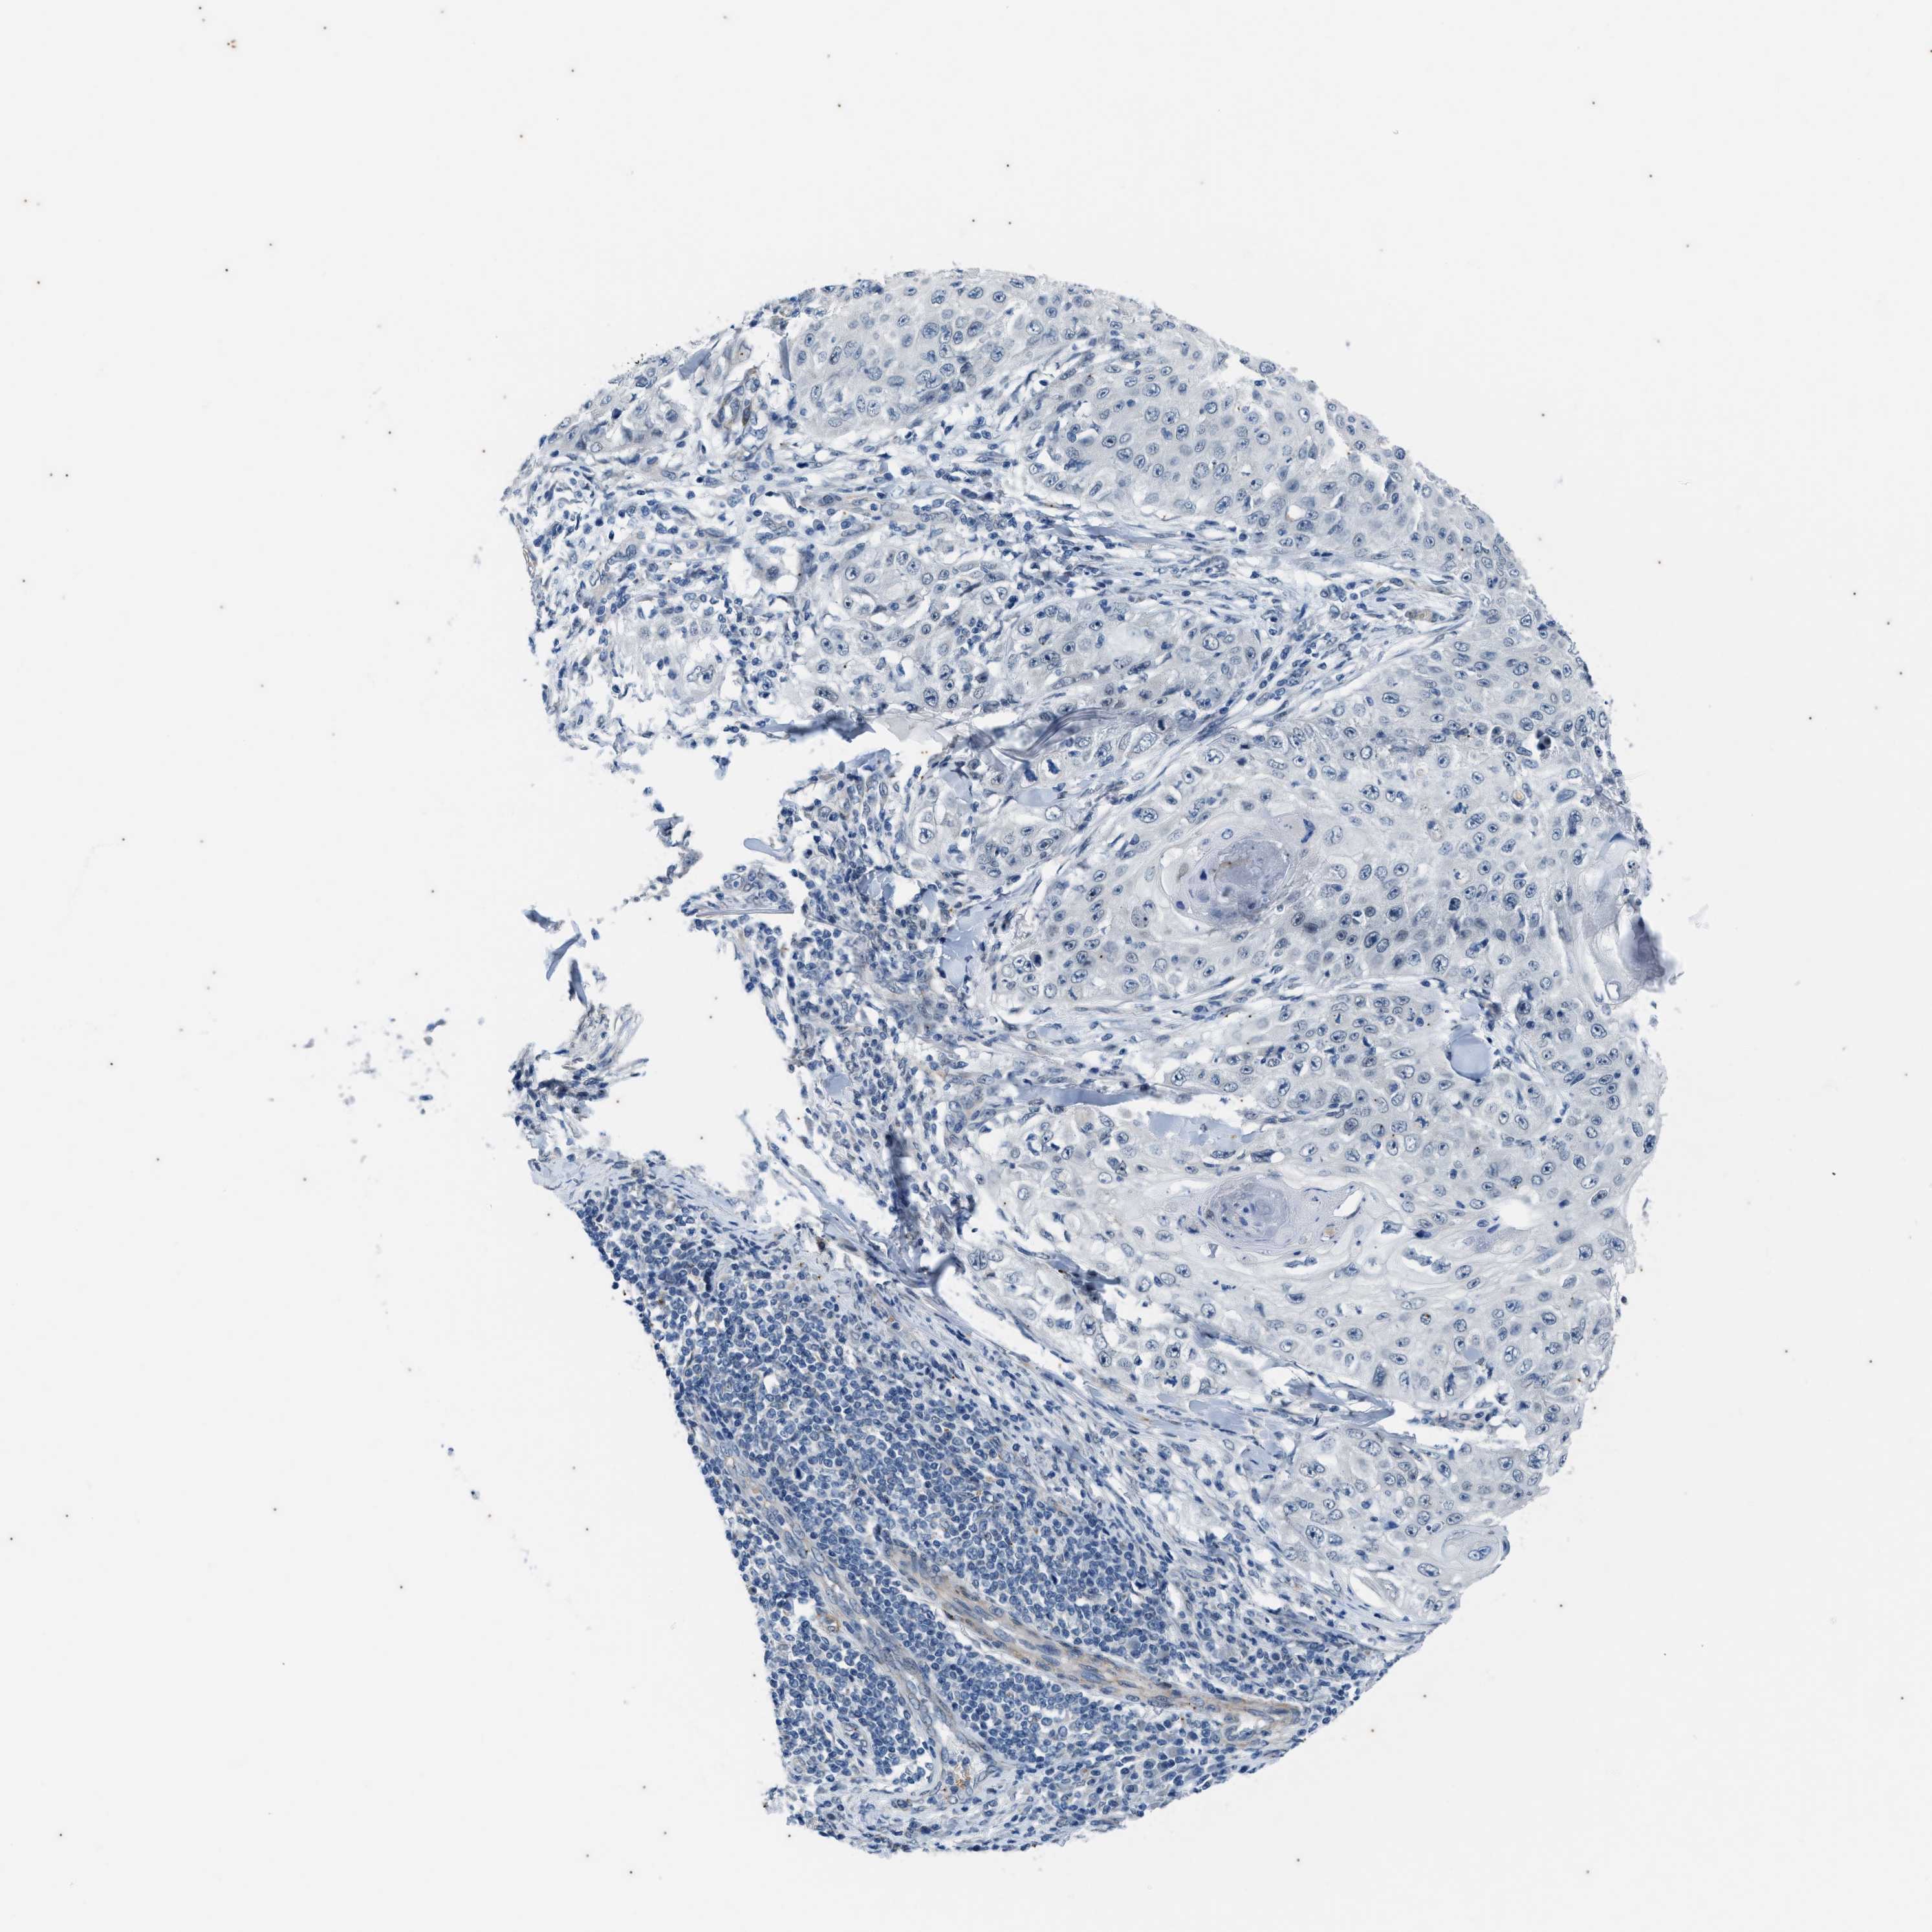

CANCER SKIN CANCER Show tissue menu

Basal cell and squamous cell cancer

SKIN CANCER - Protein expressioni

A mouse-over function shows sample information and annotation data. Click on an image to view it in a full screen mode. Samples can be filtered based on level of antibody staining by selecting one or several of the following categories: high, medium, low and not detected. The assay and annotation is described here.

Each image is clickable and will lead to virtual microscopy that enables deeper exploration of all samples and also displays staining intensity scores, fraction scores and subcellular localization as well as patient and tissue information for each sample.

Antibody HPA020643

Staining

High

Medium

Low

Not detected

Intensity

Strong

Moderate

Weak

Negative

Quantity

>75%

75%-25%

<25%

None

Location

Nuclear

Cytoplasmic/membranous

Cytoplasmic/membranous,nuclear

Basal cell carcinoma

Squamous cell carcinoma, NOS

Squamous cell carcinoma, metastatic, NOS